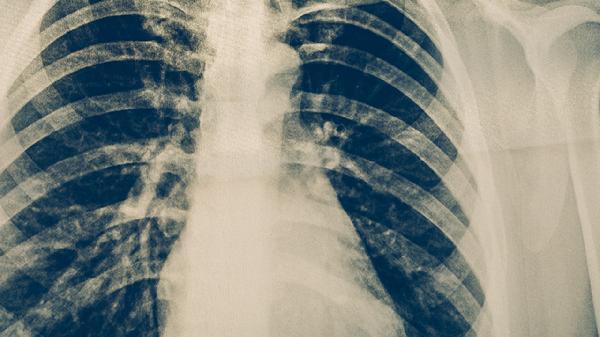

肺結(jié)核患者在治療期間一般不建議結(jié)婚。肺結(jié)核屬于傳染性疾病,治療期間可能通過(guò)呼吸道傳播給密切接觸者,且疾病本身和治療過(guò)程可能對(duì)患者身體狀態(tài)產(chǎn)生影響。

肺結(jié)核患者在抗結(jié)核治療期間需要嚴(yán)格遵循用藥規(guī)范,治療周期通常較長(zhǎng),可能需要6個(gè)月以上。治療過(guò)程中可能出現(xiàn)藥物不良反應(yīng),如肝功能異常、胃腸道不適等,這些因素可能影響患者的生活質(zhì)量和情緒狀態(tài)。結(jié)婚涉及較多社交活動(dòng)和體力消耗,可能干擾治療依從性。肺結(jié)核活動(dòng)期具有傳染性,密切接觸可能增加伴侶感染風(fēng)險(xiǎn),尤其在沒(méi)有采取充分防護(hù)措施的情況下。

肺結(jié)核患者完成規(guī)范治療且痰菌轉(zhuǎn)陰后,經(jīng)醫(yī)生評(píng)估確認(rèn)無(wú)傳染性,此時(shí)結(jié)婚更為適宜。治療結(jié)束后需要定期復(fù)查,確保疾病無(wú)復(fù)發(fā)跡象。結(jié)婚前建議伴侶進(jìn)行結(jié)核菌素試驗(yàn)或胸部影像學(xué)檢查,排除潛在感染?;楹笕孕枳⒁鉅I(yíng)養(yǎng)支持、規(guī)律作息等健康管理,避免過(guò)度勞累導(dǎo)致免疫力下降。